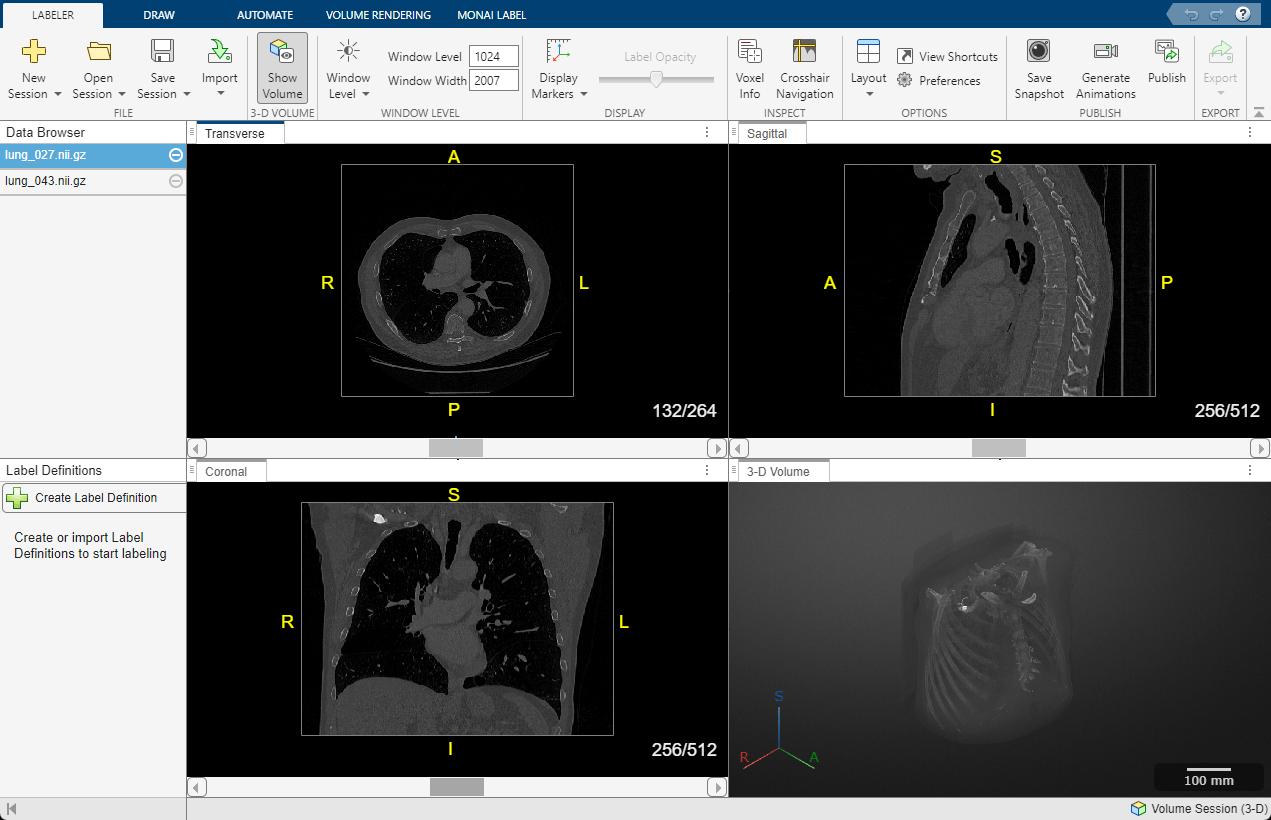

Capture d'écran montrant des images DICOM transversales, sagittales, coronales et volumétriques 3D d’une tomodensitométrie thoracique labellisé.

Tomodensitométrie (CT) thoracique 3D au format DICOM visualisé à l’aide de Medical Image Labeler dans Medical Imaging Toolbox. (Consulter la documentation